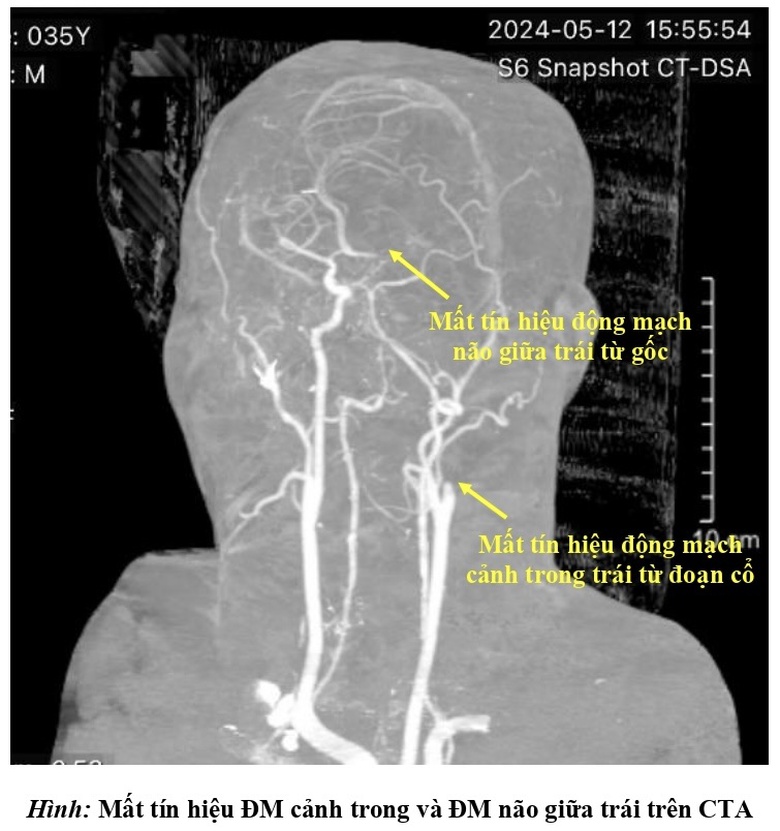

Ngay lập tức, bệnh viện kích hoạt quy trình báo động đột quỵ (code stroke). Khẩn trương thăm khám lâm sàng và cận lâm sàng, các bác sĩ chẩn đoán bệnh nhân bị đột quỵ nhồi máu não bán cầu trái giờ thứ 2 do tắc động mạch cảnh trong trái và động mạch não giữa trái bởi huyết khối.

Hình chụp CT của bệnh nhân S.

Toàn bộ bán cầu não bên trái bị ngừng cung cấp máu, đe dọa nghiêm trọng tính mạng bệnh nhân, các bác sĩ phải chạy đua với thời gian cứu chữa người bệnh.